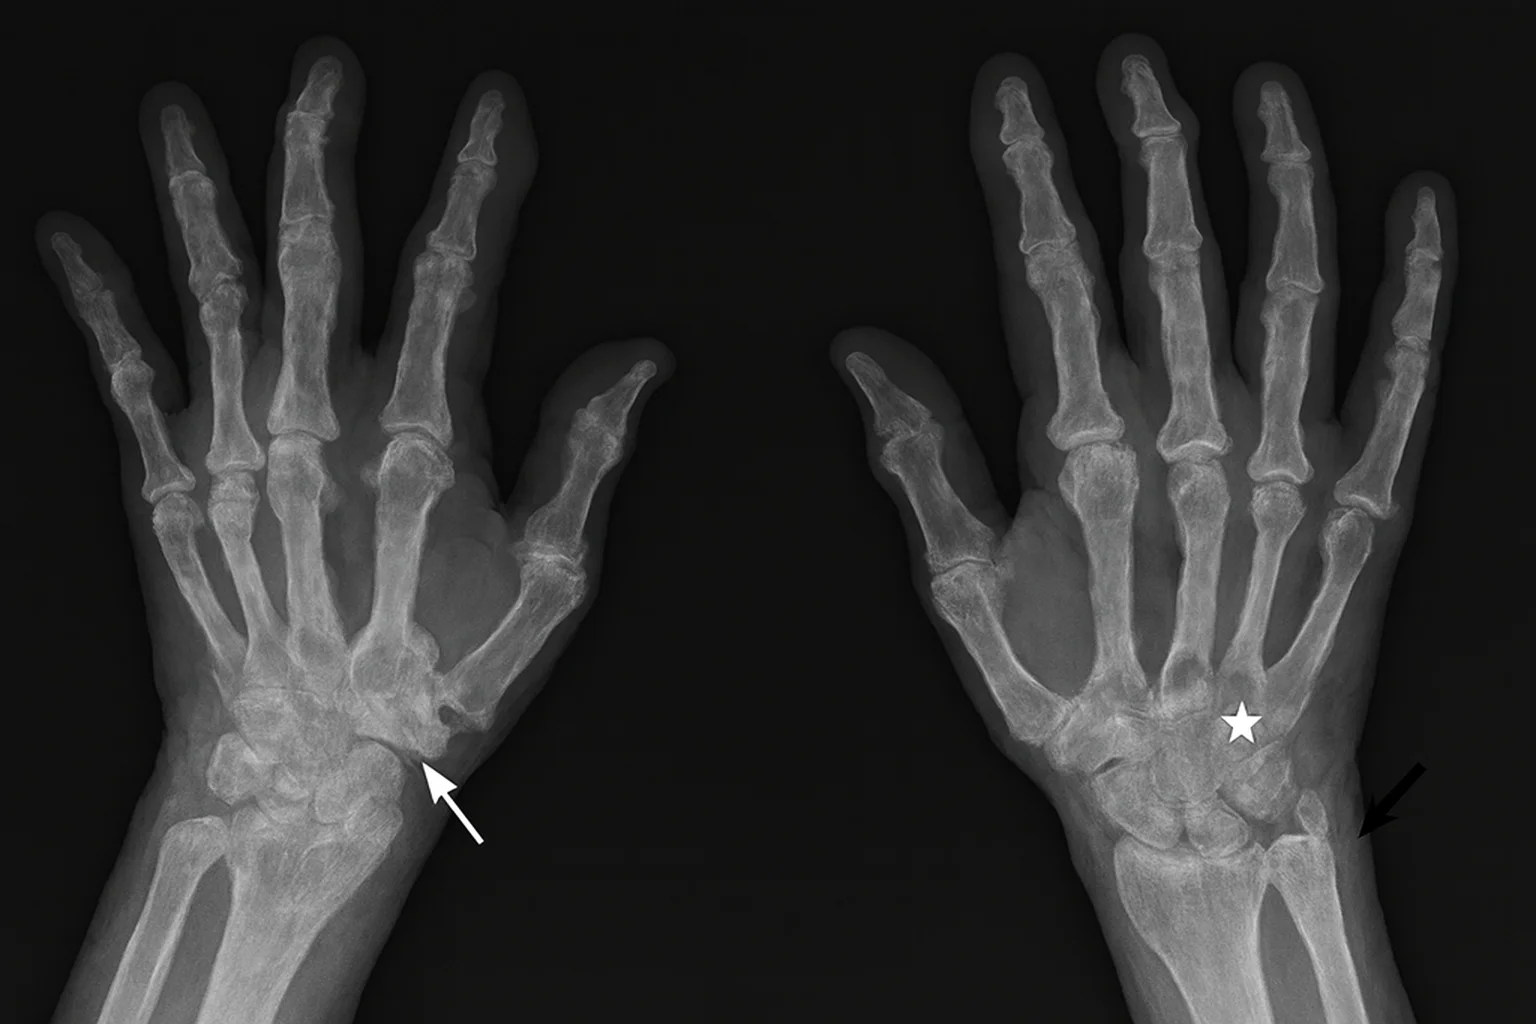

Инструментальная диагностика

Методы визуализации позволяют увидеть то, что невозможно определить по анализам:

- УЗИ суставов. Показывает утолщение синовии, отек, воспаление сухожилий.

- МРТ. Выявляет ранние эрозии, скрытый воспалительный процесс.

- Рентген. Фиксирует структурные изменения на поздних этапах.

- Допплерография. Позволяет оценить приток крови в воспаленные ткани.

Инструментальная диагностика особенно важна на ранних стадиях, когда пациент жалуется на боль, но внешних признаков поражения еще мало.

Рентгенограмма обеих кистей при серонегативном ревматоидном артрите. На снимке видны сужение суставных щелей, эрозивные изменения в области запястья, участки остеолизиса и деформация межфаланговых суставов, характерные для хронического воспалительного процесса.